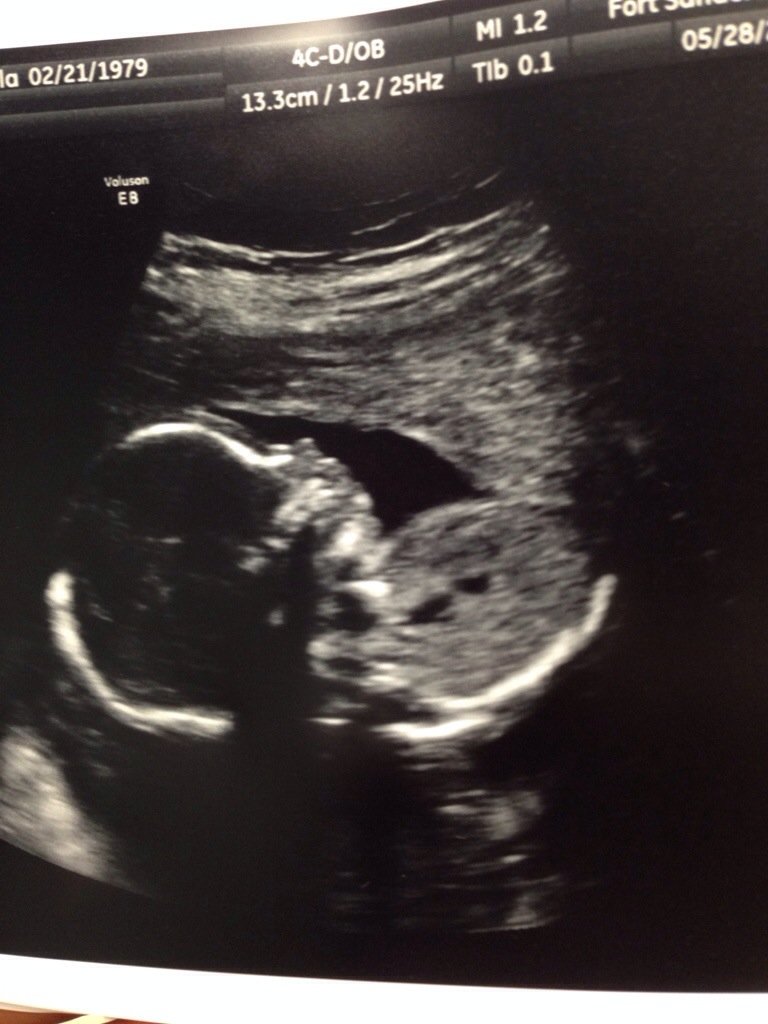

and then i heard her heartbeat, felt & saw her bouncing around. she’s healthy. she’s 1lb 6oz. her head is perfectly rounded. and even as i type this, she’s moving. we are well. life is crazy and all is well.